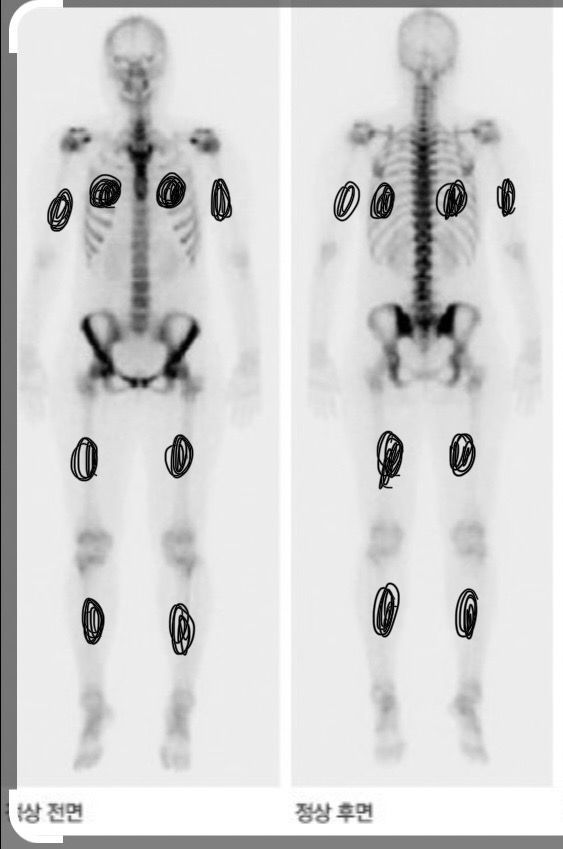

발목및 전신 뼈스캔 검사를 받았습니다 정상 소견이면 하얗게 보인다고 하는데 저는 전신에 군데군데 검은곳이 많아요…담당의(정형외과)는 다른 곳은 자기 분야가 아니어서 그런지 별말은 없었는데 저는 괜히 찜찜합니다..

**첨부한 사진은 네이버에서 정상(첫번째사진) 뼈스캔 사진으로 퍼온 사진이고 부위 설명한다고 두번째에 표시해놨습니다 (좌는 정면 우는 뒷면임)

뼈스캔 결과에서 양쪽 팔, 종아리, 갈비뼈에 대칭적으로 나타나는 검은 부분은 종종 정상 변이로 볼 수 있습니다. 이는 뼈의 대사 활동, 성장, 또는 미세한 스트레스 반응 등을 나타낼 수 있습니다. 특히 운동을 많이 하는 사람이나 특정 직업군에서 이런 패턴이 자주 관찰됩니다.

그러나 정확한 해석을 위해서는 핵의학 전문의의 판독이 필요합니다. 정형외과 의사가 별다른 언급을 하지 않았다면 심각한 문제는 아닐 가능성이 높습니다. 그러나 다른 증상이 있다면 담당 의사에게 알리고 추가 검사나 경과 관찰이 필요한지 상의해 보시는 걸 추천드립니다.